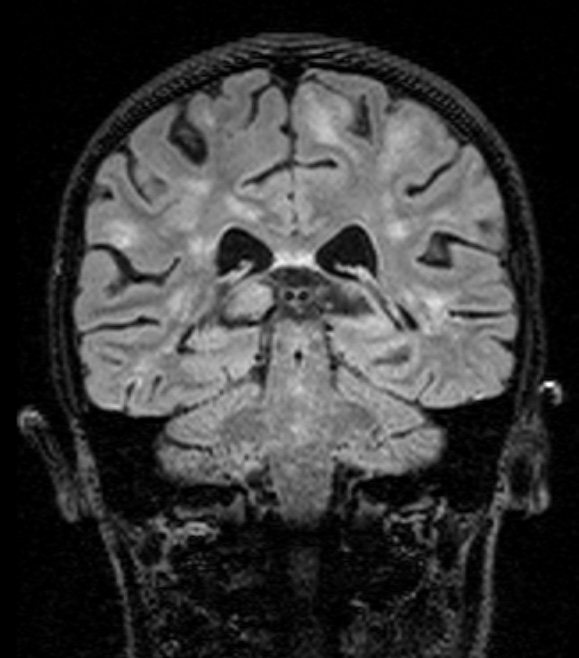

Coronal T2 FLAIR image is shown ~4 months later in the patient’s illness than the images #3A1,2. The worsening of her MRI examination at this time prompted additional workup which culminated in the diagnosis of HLH, type 2.